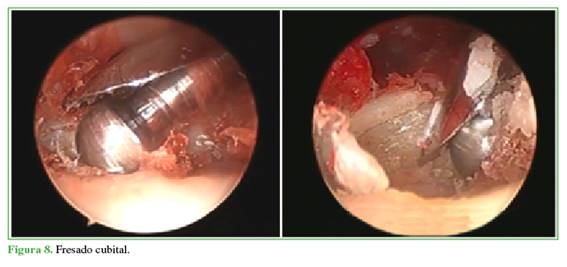

Luego de la osteotomía, se coloca la óptica por el portal dd-RCD y, por el portal 6R, se coloca una fresa orientada a la cavidad sigmoidea menor para regularizarla con exéresis de los restos de cartílago dejando una cavidad en forma de C para lograr una mayor contención (Figura 8). En este momento, se procede a la pronosupinación para evaluar la articulación con la óptica por el portal dd-RCD y confirmar que la osteotomía cubital sea adecuada. Si quedan restos óseos, se fresa sobre el cúbito para regularizar la superficie. Mediante radioscopia intraoperatoria se confirma si la osteotomía es correcta (Esquema 3).